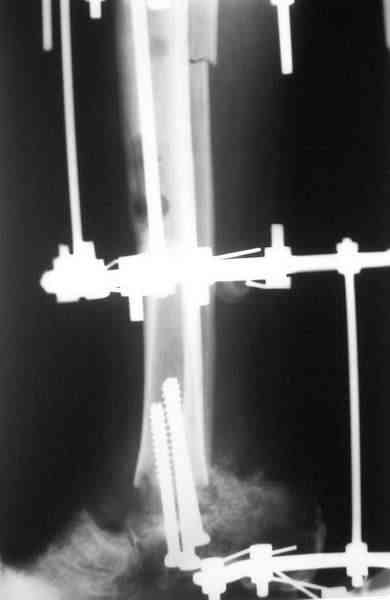

Уважаемые коллеги!Мы представляем послеоперационные рентгенограммы пациента,

ситуация с которым послужила поводом для данной дискуссии.

Нами выполнен большеберцово-пяточный артродез с фиксацией спонгиозными винтами, фиксация голени и стопы спице-стержневым аппаратом, остеотомия берцовых костей. Послеоперационный период протекает без осложнений, проводится дистраrция в аппарате.

Прилагаем послеоперационные рентгенограммы. Во время операции мы удалили кортикальный слой по передней и задней поверхностям нижнего конца большеберцовой кости и при анализе рентгенограммы может сложиться ложное впечатление, что между соединяемыми костями уложен большой костный трансплантат. Но нам удалось добиться хорошей стыковки между большеберцовой и пяточной костями.На большеберцовой кости имеются следы лечения хронического «стержневого» остеомиелита (некрсеквестрэктомия за 2 месяца перед последней операцией).